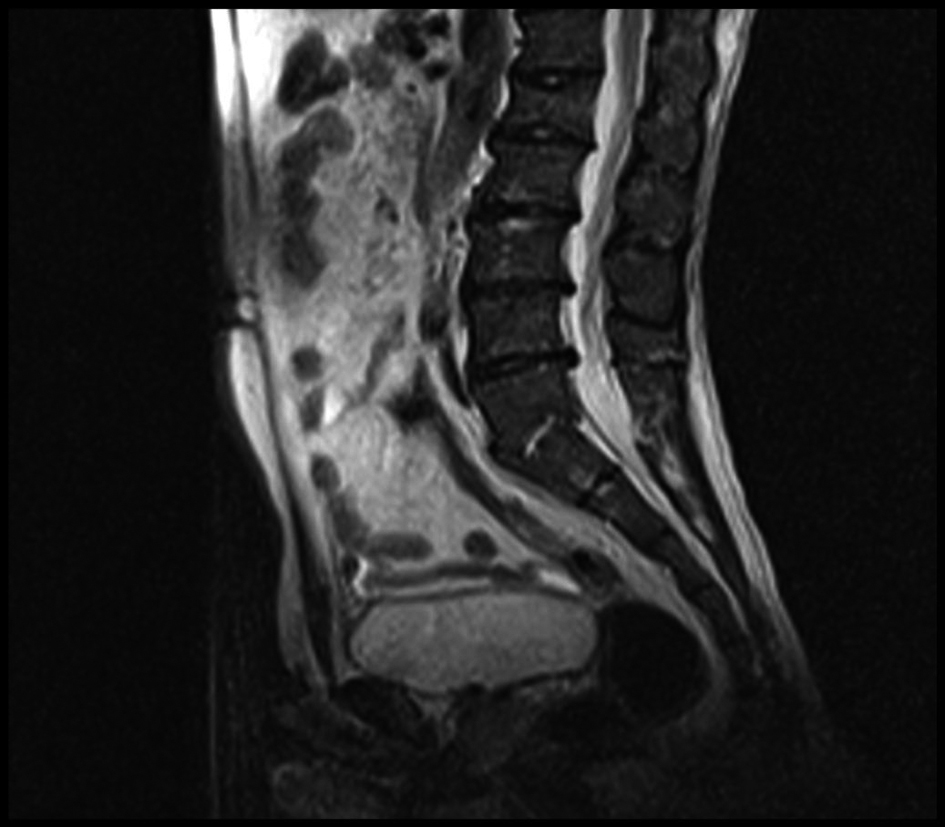

Peripheral smear, tumor markers, tuberculin skin test, Brucella and salmonella tests and bone mineral density were normal. Splenomegaly was found in abdominal ultrasonography. Widespread sclerosis of bone structures and generally irregular enhancement bilaterally in sacroiliac joints and right hip after gadolinium injection in MRI. Also it was found common degeneration in all intervertebral spaces and compression fracture at L1 vertebrae (Fig. 3, 4, 5).

![]() Click for large image | Figure 3. Lumber MRI: L1 compression fracture and dejenerations in all intervertebral. |

Clinical features and bone marrow or affected organ biopsy are used for diagnosis. Metabolic disease, malignancy and infection could not be distinguished by MRI in patient. There is no specific diagnostic finding in MRI for this disease. However, T1 weighted MRI is useful for evaluating and following skeletal involvement after treatment. T2 weighted MRI is recommended for evaluating acute bone infarcts and osteomyelitis [12].